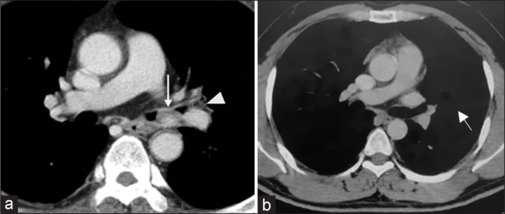

肺错构瘤是最常见的肺良性肿瘤,通常是偶然发现的。支气管内错构瘤虽然罕见,但可引起明显的症状,如呼吸困难、咯血和支气管阻塞引起的反复呼吸道感染。本报告描述两名年龄分别为29岁和34岁的年轻印度男性成功的支气管镜治疗有症状的支气管内错构瘤。这两个病例都是根据放射学和组织病理学结果诊断的。第一名患者使用柔性支气管镜进行了8次电灼,而第二名患者通过柔性支气管镜引导的冷冻探针进行了6次冷冻治疗。所有手术均在清醒镇静下进行,通过柔性支气管镜鼻腔插入,不需要刚性支气管镜或全身麻醉。两例患者均表现出明显的症状改善和支气管内病变几乎完全消退。分别在18个月和12个月随访支气管镜检查,未发现复发,也未观察到手术相关并发症。这些病例强调了柔性支气管镜技术如电灼和冷冻消融治疗支气管内错构瘤的安全性、有效性和微创性,特别是在手术选择可能有限的情况下。

Pulmonary hamartomas are the most common benign tumours of the lung and are often detected incidentally. Endobronchial hamartomas, though rare, can cause significant symptoms such as dyspnoea, haemoptysis, and recurrent respiratory infections due to bronchial obstruction. This report describes the successful bronchoscopic management of symptomatic endobronchial hamartomas in two young Indian males aged 29 and 34 years. Both cases were diagnosed based on radiological and histopathological findings. The first patient underwent eight sessions of electrocautery fulguration using a flexible bronchoscope, while the second was treated with six sessions of cryotherapy delivered through a flexible bronchoscope guided cryoprobe. All procedures were carried out under conscious sedation via nasal insertion of the flexible bronchoscope, with no requirement for rigid bronchoscopy or general anaesthesia. Both patients showed marked symptomatic improvement and near-complete resolution of endobronchial lesions. Follow-up bronchoscopies at 18 and 12 months, respectively, revealed no recurrence, and no procedure-related complications were observed. These cases highlight the safety, efficacy, and minimally invasive nature of flexible bronchoscopic techniques such as electrocautery and cryoablation in managing endobronchial hamartomas, particularly in settings where surgical options may be limited.